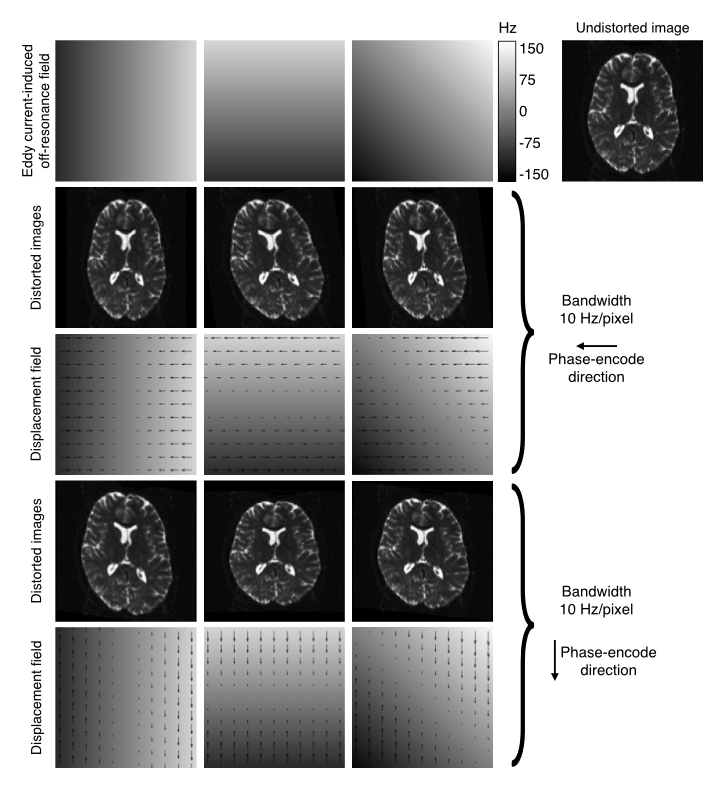

| Explanation of how EC-fields translate into distortions. |

![]() |

| The top row shows EC-fields linear in the $x$, $y$ and $xy$-directions in columns 1-3 respectively. The fourth column shows an undistorted image. Row two shows the resulting distorted images for data acquired with the phase-encoding in the $y$-direction, and row three shows the corresponding displacement fields. Rows four and five shows the same for the case where the phase-encoding is in the $y$-direction. |

The fields and distortions in the figure above still assume that the EC-fields are "perfect" linear combinations of linear gradients. However, that is not a given and there is ample evidence that this is not generally true (I would personally go as far as to say the it is generally not true). When validating eddy on the HCP data we found strong evidence both for quadratic and cubic terms, even though the cubic terms where sufficiently small to safely ignore even though they could be reliably detected.